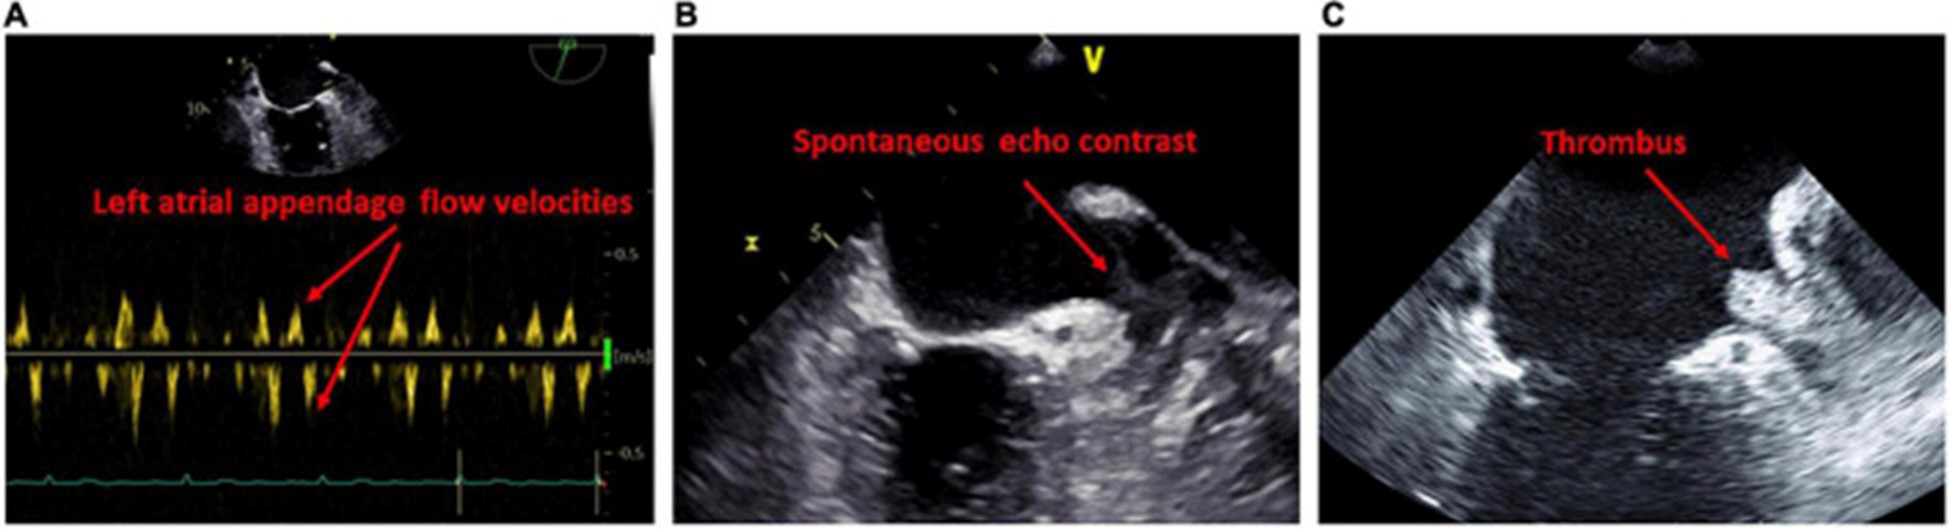

经食道超声心动图

经食道超声心动图的一个重要优势是更精确地评估左心耳。关于经食管异常与左心房心肌病相关性的证据有限,LACM 主要通过延迟增强 MRI 确定纤维化来确定。经晚期钆增强 MRI 诊断,与没有血栓的患者相比,有 LA 附肢血栓的患者有更多的 LA 纤维化 。有自发回声对比的患者的 LA 纤维化程度甚至高于没有的患者。此外,高心房纤维化患者更可能在左心耳同时出现血栓和自发回声对比(70)。众所周知,LA/LA 附件血流动力学减少和 LA 大小增加是血栓和自发回声对比发生的危险因素 (图 4)。

图 4:经食道检查提示左心房心肌病的结果。(A)左心耳口的血流减少。(B)左心耳自发回声对比的证据。(C)左心耳血栓的证据。